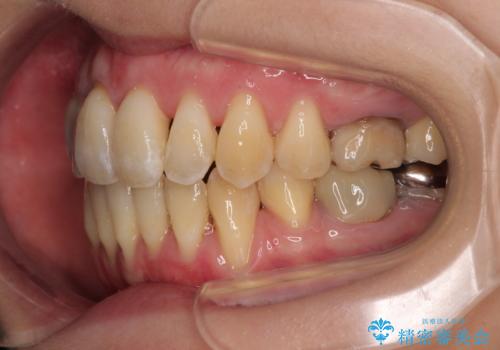

急速拡大装置 狭い骨幅を拡大した上で、顕著なデコボコを改善する抜歯矯正治療

上顎骨よりも下顎骨の幅が広く、更には下顎骨が左側に変位していたため、より良い咬み合わせを達成することを目的として、急速拡大装置を用いて上顎骨を拡大することとしました。

デコボコが強い上に、口元の突出感も気にしていたため、上下左右の小臼歯4本を抜歯して、ワイヤー装置にて矯正治療を行うこととしました。

歯根露出が顕著であったため、歯の移動は早く、スムーズに治療を終えられるかと思いましたが、歯槽骨が硬く、治療は長期間に及びました。

過剰に力をかけ続ける事態となり、一部の歯では変色したり、神経が失活したりとトラブルが続きました。

それでも当初とは比べものにならないほど、綺麗な歯列に仕上げることができました。